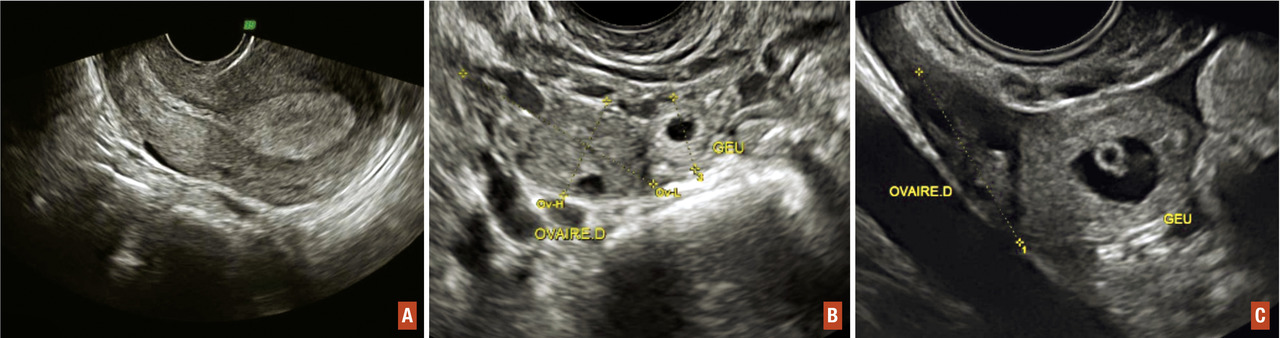

Elle constitue l’examen clé du diagnostic. Elle doit être réalisée par voie abdominale, puis par voie endovaginale à vessie vide. L’espace de Morrison situé entre le foie et le rein droit doit être systématiquement examiné par voie abdominale. La présence d’un épanchement dans cet espace signe la présence d’un hémopéritoine abondant (fig. 2).

L’échographie par voie endovaginale visualise (fig. 3) des signes indirects tels que :

• un endomètre épaissi ;

• une vacuité utérine ;

• un épanchement péritonéal en cas de grossesse ectopique compliquée d’une rupture tubaire ;

ou des signes directs :

• une masse latéro-utérine entre l’utérus et l’ovaire qui est constituée d’un sac gestationnel dans seulement 20 % des cas (où il faut alors rechercher un embryon et une éventuelle activité cardiaque). Dans la majorité des cas, il s’agit d’une masse hétérogène (hématosalpinx ou trophoblaste intratubaire).